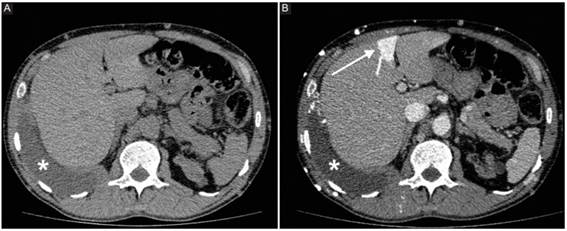

El signo del punto caliente se describe como un área de parénquima hepático de mayor captación de contraste endovenoso (Fig. 1), generado por la presencia de colaterales entre la vena cava superior (VCS) y la vena porta, debido a una obstrucción en el primer nivel mencionado. En 1989, fue inicialmente descripto por Yedlicka et al. en estudios de medicina nuclear con azufre-tecnecio99 como un área de mayor captación del trazador1.